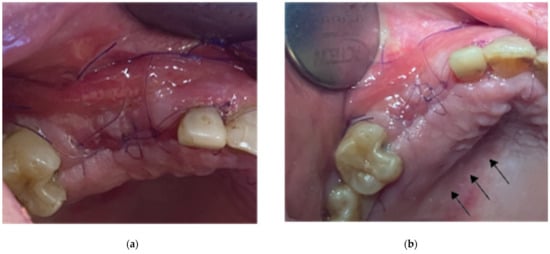

- A palatal incision parallel to the alveolar ridge and located apically nearly 15 mm from the marginal palatal soft tissue, leaving the periosteum intact, was performed prior to the placement of sutures. Then, a split-thickness preparation below the palatal flap was performed until the dissected area reached the incision limits. After confirmation of the communication between both entries, the palatal flap coronal advancement was possible, ensuring a primary closure.

- An intermediate layer of horizontal mattress monofilament absorbable Glycolon 4.0 adaptation sutures (Resorba, Nuremberg, Germany) was placed below the muco-gingival line to secure an additional stabilization of the cortical barrier on both the buccal and the palatal side and the coronal advancement of both flaps.

- A superficial layer of vertical mattress (placed at the papillary areas between the teeth adjacent to the augmentation site), along with simple interrupted Glycolon 5.0 (Resorba, Nuremberg, Germany) closure sutures (placed at the inter-proximal abutment areas), provided primary flap closure and papilla stabilization on their initial pre-operative position.

- A superficial incision, performed with a 15 blade deep in the vestibule, was finally used to reduce muscle pulling during the post-operative healing period.